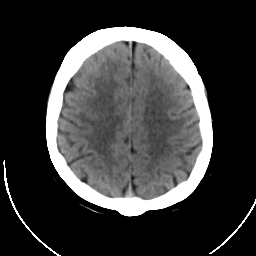

CT Study #1 -- Slice #17